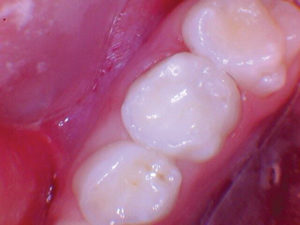

|

Figura 1. Después del ataque ácido y el uso del agente de unión Scotchbond Universal (3M), los dos molares primarios superiores se restauraron con Activa Bioactive Restorative A2. |

Figura 2. Una vez que se excavó la descomposición y se colocaron los márgenes en superficies sólidas, se colocó un bisel pesado en el esmalte para aumentar la resistencia de la unión y la integridad marginal. El área oscura central era sólida. El diente estaba revestido con una base / revestimiento Activa. |